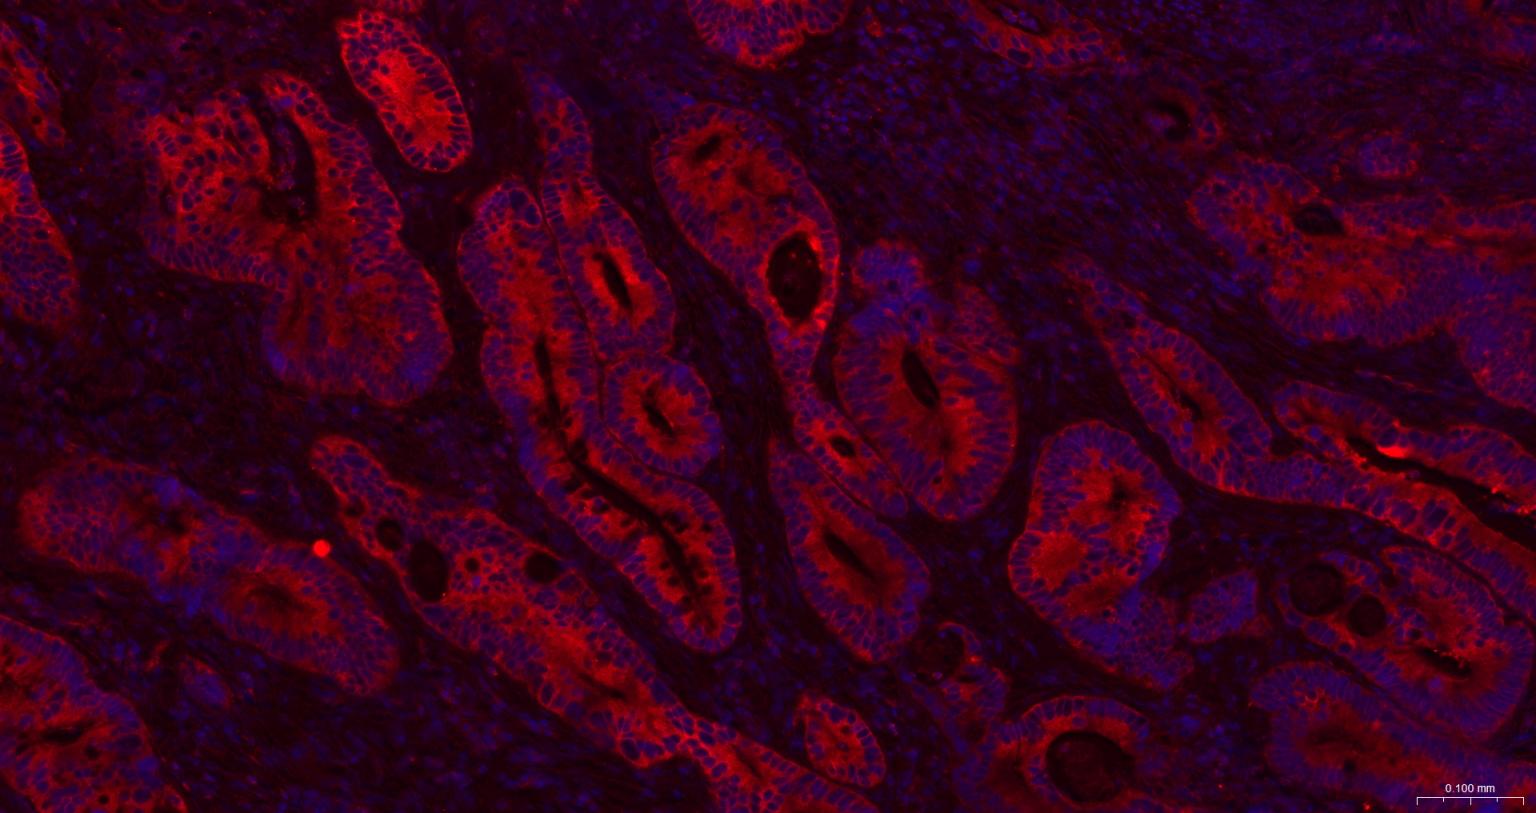

Paraformaldehyde-fixed, paraffin embedded Human Colon Cancer; Antigen retrieval by boiling in sodium citrate buffer (pH6.0) for 15 min; The section was incubated with GART Monoclonal Antibody, Unconjugated (bsm-52537R) at 1:200 overnight at 4°C. Followed by conjugated Goat Anti-Rabbit IgG antibody (Red, bs-0295G-BF594), DAPI (blue, C02-04002) was used to stain the cell nuclei.